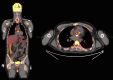

A 38-year-old patient with a prosthetic aortic valve had weeks of fever and respiratory symptoms. Although endocarditis was suspected early, numerous blood cultures and echocardiograms failed to confirm the diagnosis. Key questions were: What is a broad differential diagnosis for the above symptoms? What is unique about diagnosing prosthetic valve endocarditis compared with native valve endocarditis? What other imaging modalities are useful for diagnosing prosthetic valve endocarditis when initial echocardiographic evaluation is negative? What organisms are classically implicated in "culture negative" infective endocarditis? Serial blood cultures and multimodal imaging, including cardiac positron emission computed tomography with 18F-fluorodeoxyglucose, lead to a diagnosis of prosthetic valve endocarditis with a HACEK (Haemophilus, Aggregatibacter, Cardiobacterium, Eikenella, Kingella) pathogen. Repeat blood cultures and serial multimodal imaging are paramount to diagnosing prosthetic valve endocarditis, particularly when caused by a fastidious organism.